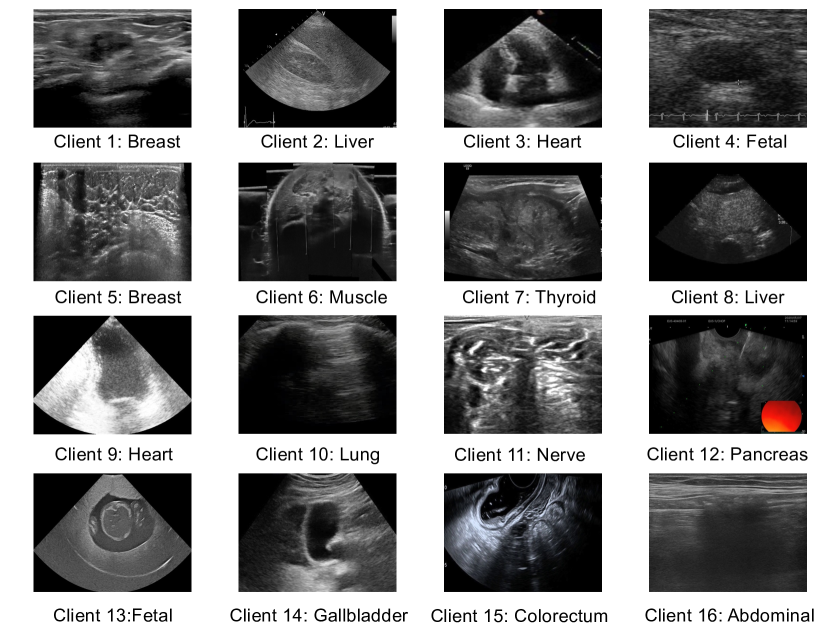

In this work, we introduce UltraFedFM, a novel ultrasound foundation model pre-trained collaboratively by multiple medical institutions without exposing and aggregating all the data together. Specifically, we utilize a federated learning framework with one server and 161616 clients from 999 countries, collectively possessing 1,015,75410157541,015,754 unlabeled ultrasound images (Fig. 1a). These images cover 19 systemic organs and 10 ultrasound imaging modalities (Fig. 2a-b), providing extensive and diverse representation for pre-training. The development of UltraFedFM consists of two stages: (1) Federated pre-training, in which the multiple clients collaboratively pre-train a shared model in a distributed, self-supervised manner. Throughout the pre-training process, the server periodically aggregates the local model parameters from each client without accessing their private data (Fig. 1b); (2) Downstream fine-tuning, where the pre-trained FM is fine-tuned using specific data to adapt to various clinical tasks, such as disease screening and diagnosis, sub-classification of disease phenotypes (e.g., tumor infiltration depth and type classification), prenatal maternal-fetal health analysis, and critical lesion identification and segmentation (Fig. 1c).

Table 1: Summary of the pre-training datasets and the data distributions of all local clients.

Clients Nmae Location Main US Madality Main Organ Numbers

Client 1 BUV [5] Hong Kong, China Superficial Breast 25,727

Client 2 CLUST [31, 32] Switzerland Abdominal Liver 35,626

Client 3 EchoNet-Dynamic [33] California, USA Echocardiogram Heart 150,243

Client 4 FETAL-PLANES[6, 34] Spain Fetal Fetal organs 12,400

Client 5 TDSC-ABUS [35] Harbin, China 3D Abdominal Breast 126,918

Client 6 Leg-3D-US [36] German 3D Muscle Muscle 115263

Client 7 Thyroid Ultrasound Cine-clip [15] California, USA Superficial Thyroid 17,412

Client 8 SYSU-FLL-CEUS [37, 38] Guangzhou, China Abdominal Liver 118,485

Client 9 CAMUS [39] France Echocardiogram Heart 21,214

Client 10 COVID-BLUES [40] United Kingdom Lung Lung 42,226

Client 11 NerveUS [12] Georgia, USA Superficial Nerve 11,143

Client 12 LEPset [41] Chongqing, China Abdominal Pancreas 11,499

Client 13 FPUS [42] Austria Maternal-fetal Fetal organs 20,378

Client 14 GBUSV [43] India Abdominal Gallbladder 10,553

Client 15 ERUS Sichuan, China Endorectal Colorectum 63,426

Client 16 PrivateUS Sichuan, China

Abdominal,

Maternal-fetal,

Superficial,

Echocardiogram

Uterus, Vascular, Stomach,

Spleen, Prostate, Testis,

Paratod Gland, Lymph Nodes

235,633

Refer to caption

Figure 9: Sample images of each client in the pre-training dataset.